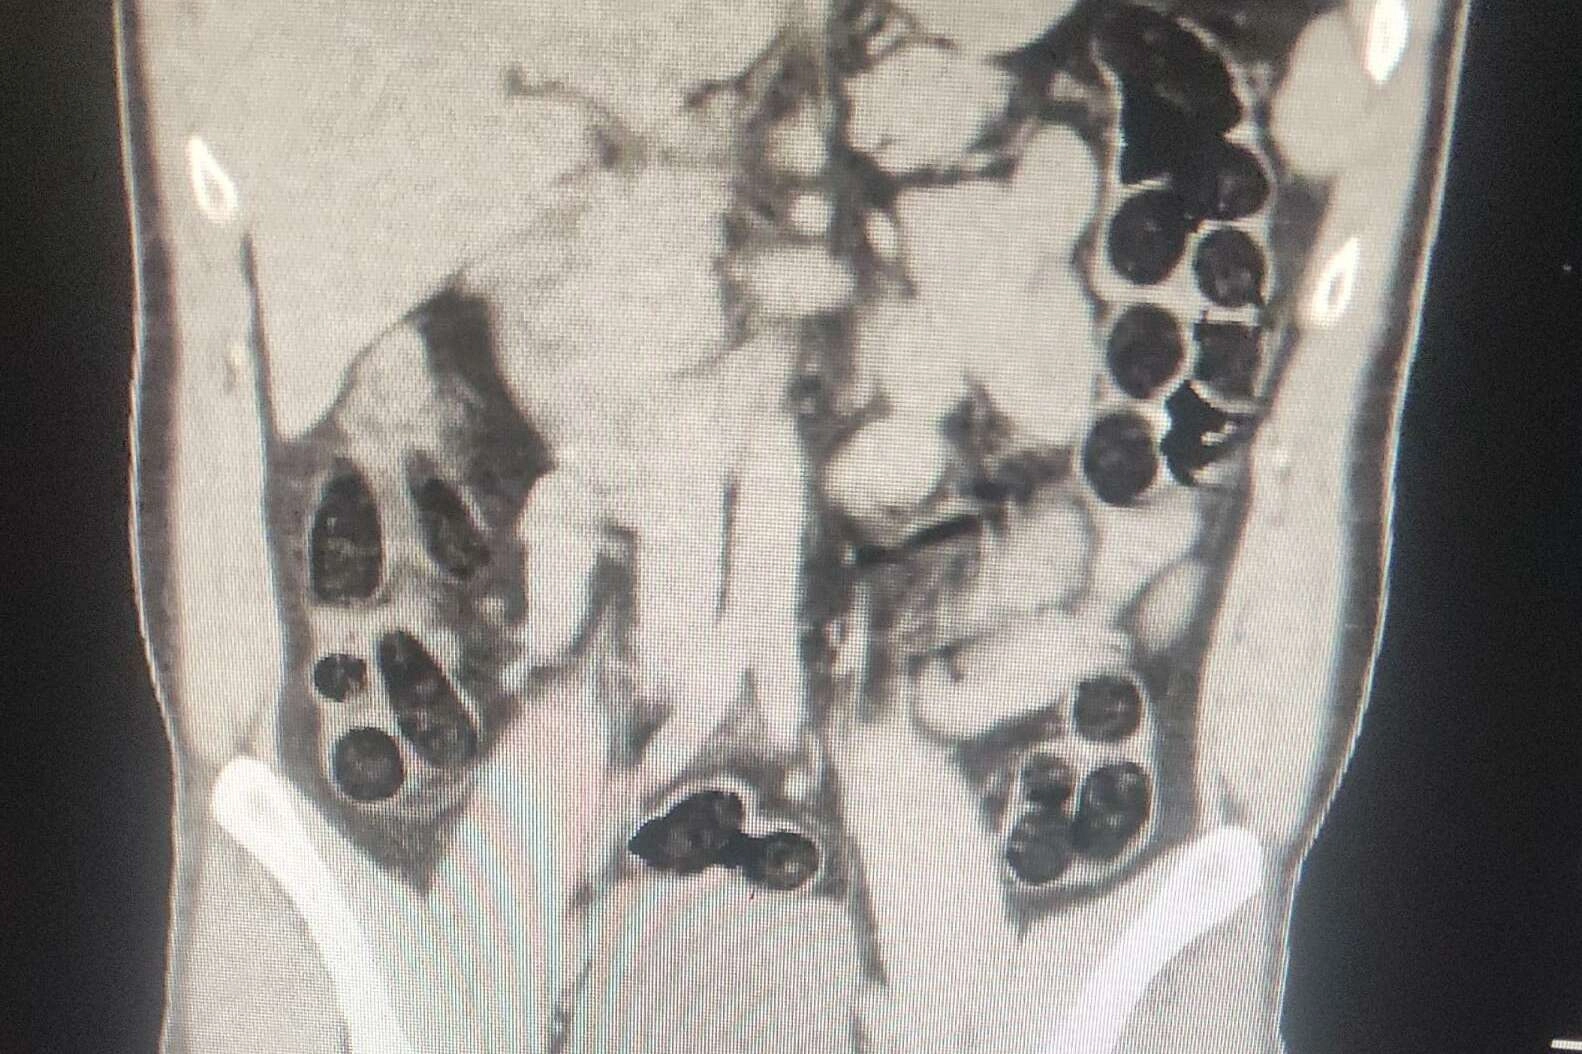

Batman Valiliğinden yapılan açıklamada, otobüs firmaları üzerinden yolcu olarak seyahat eden şahısların batı illerine yüklü miktarda uyuşturucu madde sevk edileceği bilgisi üzerine operasyon yapıldığı bildirildi. Operasyonda; otobüs ile seyahat eden 2 İran uyruklu şahsın yapılan kontrollerinde ve iç beden muayenesi sonucunda, şahıslardan birinin midesinde 76 paket halinde, 714 gram eroin maddesi ele geçirildiği belirtildi.